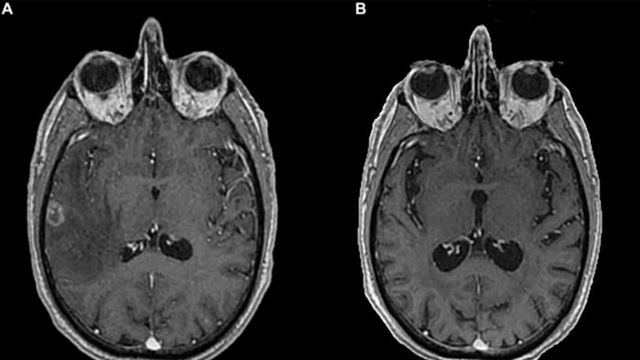

Brain MRI at diagnosis and last Brain MRI performed.

Complete Response to Immunotherapy in Stage IV Lung Cancer

A case report highlights a 51-year-old man with stage IV non-small cell lung cancer and brain metastasis who received whole brain radiotherapy followed by immune checkpoint inhibitor treatment.